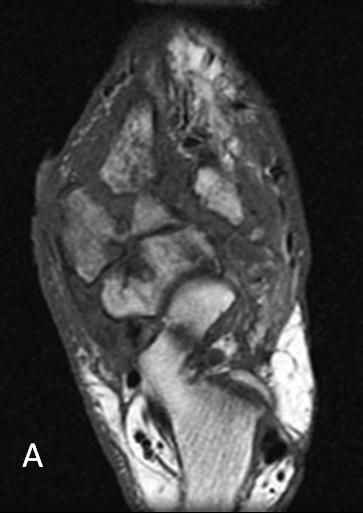

Figure 2A

T1-weighted (

A

) and T2-weighted (

B

) MRI scans depict diffuse intermedullary changes to the midtarsal bones with consolidated fragments, subluxations, and dislocations resulting in a gross deformity throughout the midfoot.Figure 2B

T1-weighted and T2-weighted MRI scans (Figure 2) depict diffuse intermedullary changes to the midtarsal bones with consolidated fragments, subluxations, and dislocations, resulting in a gross deformity throughout the midfoot.